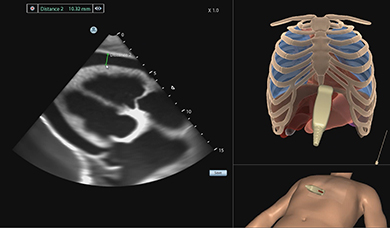

Simbionix Ultrasound Mentor is the answer to the growing need for ultrasound training among multiple medical specialties. This modular simulation platform enables easy manikin rotation (male, female, pediatric and interventional), and offers diverse applications for a range of specialties such as OB/GYN, Point-of-care Ultrasound (POCUS) and Echocardiography.

Ultrasound Mentor accelerates the development of basic to advanced technical and cognitive skills, by providing not only the probe manipulation training, but also a didactic environment enabling structured, self-guided learning including step-by-step instructions and educational aids such as 3D anatomical map and probe positioning assistant, all backed up with our progress monitoring tool MentorLearn.

Bedside Echocardiography Module

Advanced Echo Module

TEE Module

TEE Emergency Module

Simulation-based teaching of TEE showed a significant improvement in the knowledge, skills, and self-assessment of proficiency of cardiology fellows, as well as a reduction in the amount of time needed to complete the examination. These results should encourage further investigation of clinical performance and patient benefits of TEE simulation training.